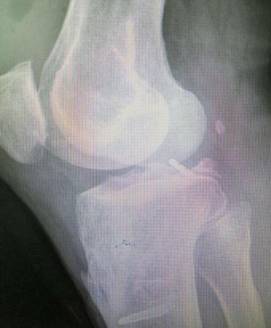

胫骨高位截骨治疗膝关节骨关节炎

优点:创伤小,疗效确切,适合生活方式活跃的年轻患者。

术前术后对比